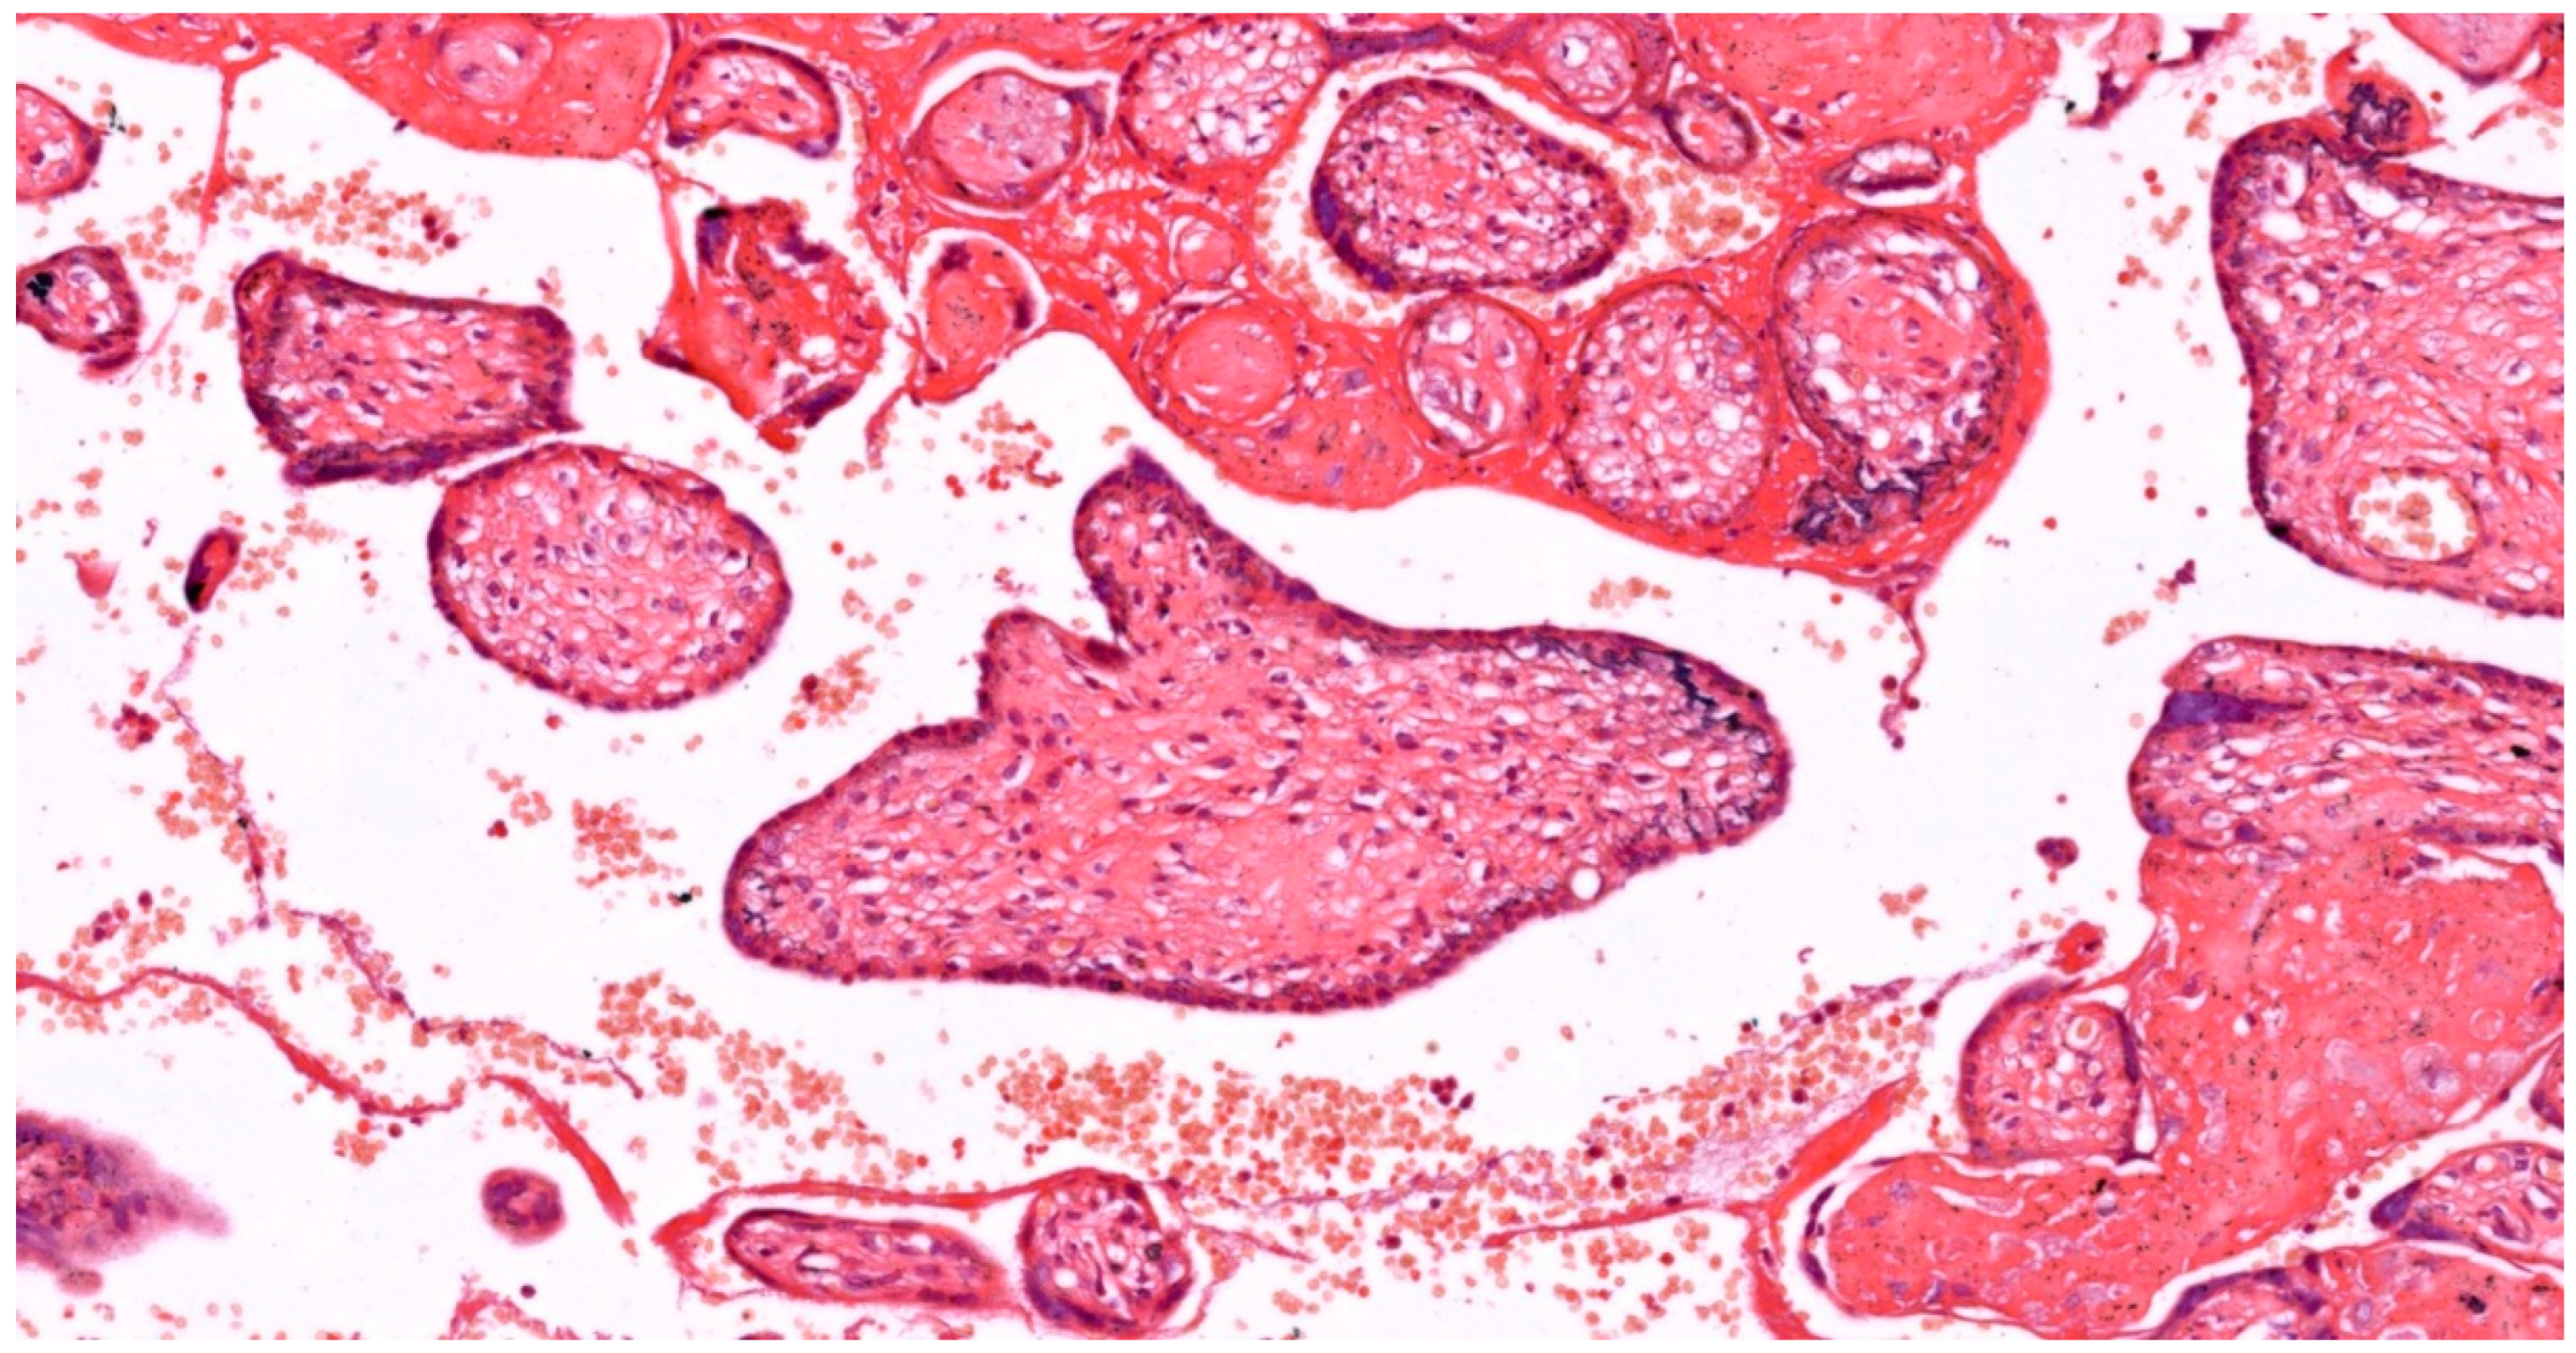

| Pathology | Role of Oxidative Stress | Histological Features |

|---|---|---|

| Maternal Vascular Malperfusion | - Impairs trophoblast invasion - Causes endothelial dysfunction - Increases villous trophoblast apoptosis |

- Decidual arteriopathy - Accelerated villous maturation - Distal villous hypoplasia - Increased syncytial knots - Infarction and retroplacental hemorrhage |

| Gestational Trophoblastic Diseases | - Implicated in abnormal trophoblast proliferation and differentiation - Alters angiogenesis |

- Hydropic swelling of villi - Trophoblast hyperplasia - Abnormal vasculature |